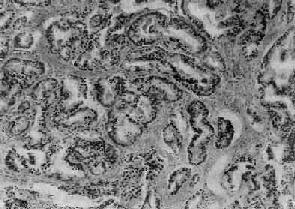

图14-4 前列腺癌(高分化型) 腺体密集,癌细胞体积较小,核深染,上皮细胞呈多层排列并较不规则,可见间质浸润

二、前列腺癌前列腺癌(carcinoma of prostate)多发生于60岁以上的老年人,在我国远较欧美国家少见。美国报告前列腺癌的死亡率占恶性肿瘤死亡率的第二位,在我国前列腺癌的发生率只占恶性肿瘤的0.3%左右。 【病因】 前列腺癌的病因尚不十分清楚,一般认为激素特别是雄激素可能起重要作用。长期以来各家对前列腺癌与前列腺增生之间的关系看法不一。目前大多数学者认为两者间无明显关系,因为前列腺癌很少发生于良性增生的前列腺内。在组织发生上增生与癌的发生部位也不相同,前列腺增生多发生于尿道周围部的前列腺组织(即前列腺内区);而前列腺癌几乎都开始发生于前列腺的包膜下部(即前列腺外区),该部组织对雄激素敏感,高水平的雄激素可使该部增生。据统计,阉人不发生前列腺癌,这些都支持雄激素和前列腺癌有关。但前列腺癌患者多为老年人,睾丸产生的雄激素已经降低,所以仍有不支持此说的根据。有人假设前列腺癌发展很慢,可以长期处在潜伏状态,可能在雄激素尚处于较高水平时即已发生小的癌灶,发展到老年才出现症状,这一假设尚有待进一步验证。 【病变】 肉眼观,前列腺癌初期为单个或多数的硬结节,其前列腺可以增大,也可正常大小。早期病灶几乎都发生于包膜下,其中大多数发生于后叶,其次是两侧及前叶的包膜下,而发生于中叶者极为少见。晚期肿瘤可扩展到全部前列腺,使前列腺明显增大而质地变硬。切面灰白色夹杂以多少不等的纤维性条纹或间隔,也可呈均质性夹以不规则的黄色区域。 镜下,97%的前列腺癌均为腺癌,少数为移行细胞癌和鳞状细胞癌。依其分化程度可分为高分化、中分化和低分化3型。高分化前列腺癌最多见,癌细胞排列成大小不等的腺样结构,颇似前列腺增生腺体,但癌细胞体积较小,核较深染,上皮细胞往往呈多层排列并较不规则(图14-4),有时可呈乳头状腺癌或腺泡腺癌结构,并常可见癌组织向间质浸润生长;中分化腺癌全部或部分呈腺样结构,但腺体排列较紊乱,核异型性较明显,且有时形成筛状结构;低分化腺癌的癌细胞一般较小,排列成实体团块或条索,腺腔样结构很少(图14-5)。多数病例乃由上述多种组织结构混合组成。